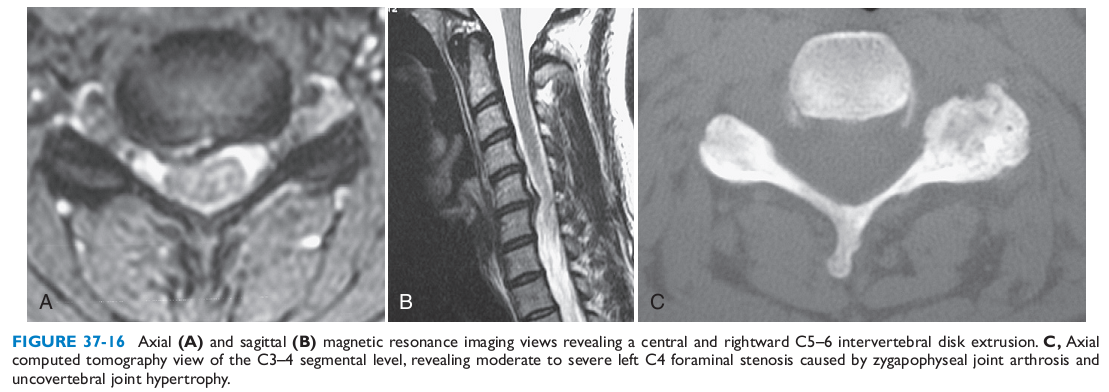

Chụp cộng hưởng từ (MRI).

- Phát hiện các bất thường của đĩa đệm (thoái hóa, thoát vị), dây chằng (phì đại, cốt hóa), chèn ép rễ thần kinh và tủy sống

Chụp CT cột sống cổ:

- Phát hiện rõ hơn những bất thường của xương như gai xương, thoái hóa, hẹp ống sống và lỗ gian sống…

hình ảnh thoát vị đĩa đệm C5-6 trung tâm lệch trái.

CT scan (C) đoạn C3-C4 cho thấy hẹp lỗ ghép do phì đại khớp, thoái hóa.